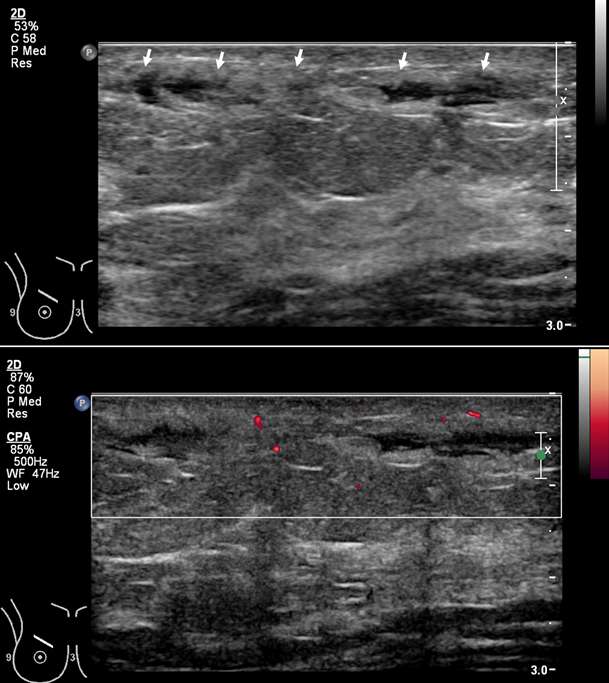

Superficial thrombophlebitis of the breast, or Mondor disease, is a superficial veno-occlusive disease most commonly involving the thoracoepigastric, lateral thoracic, or superior epigastric veins of the upper outer or upper inner quadrants, or inferior breast and chest wall. The clinical presentation varies with acuity, ranging from incidental and asymptomatic, to a focally painful palpable “cord” with associated yellowish or purplish skin discoloration and/or skin retraction or dimpling. The condition most often affects women in their third to sixth decade of life (75%) but can also occur in men. Causative factors are shared with other common causes of thrombophlebitis outside of the breast, and include trauma, post biopsy/surgery, botulinum toxin or other injections, pregnancy, breast cancer, and other hypercoagulable states. However, the majority of cases of Mondor disease are idiopathic. Ultrasound is the gold standard in diagnosis, which classically shows a noncompressible hypo- or anechoic superficial tubular or beaded structure, occasionally with demonstrable wall thickening and inflammatory changes (Figure 3A-B). Color Doppler shows minimal to no flow. Chronic thrombosis may result in vascular calcification, which may be seen as hyperechoic intraluminal foci with posterior shadowing or comet tail artifact. The disease course is often self-limited, with most cases resolving spontaneously over 2-12 weeks. Treatment is supportive with over-the-counter analgesics (e.g., ibuprofen, acetaminophen) as needed for pain. Importantly, there is no role for antibiotics or anticoagulation therapy, as Mondor disease is not infectious in origin and by definition does not involve the deep venous system.